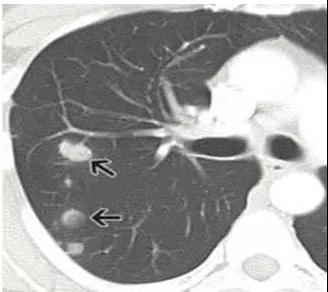

4、肺部的良性腫瘤

比如錯構(gòu)瘤、血管瘤等良性的腫瘤,也可以表現(xiàn)為肺結(jié)節(jié)。

錯構(gòu)瘤可以理解為長錯了地方的正常組織,比如一些軟骨成分長在了肺里面,這與先天發(fā)育有關(guān)。